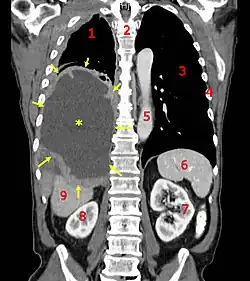

![]() A coronal CT scan showing a malignant mesothelioma, indicated by the asterisk and the arrows | |